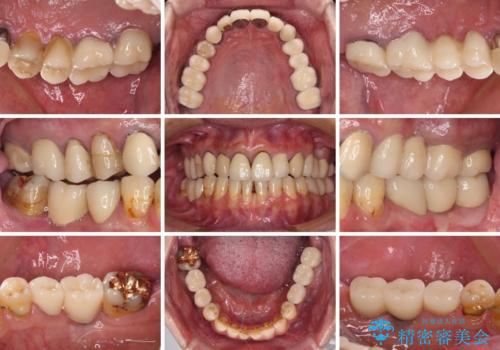

下顎の部分矯正を行ってから奥歯の補綴治療とインプラント治療

- 抜歯した歯や抜歯が必要と思われる歯を放置したため、奥歯に不快を感じているとのことで来院された患者様です。

右下は奥歯が抜歯したスペースを塞いでしまい、左下はブリッジの支台歯の1つが破折している状態でした。

また、下顎前歯にはスペースがあり、コンポジットレジンでスペースを閉じている状態だったので、前歯のスペースを解消しつつ、奥歯にスペースを獲得するよう矯正治療を行うこととしました。

並行して左下にはインプラントを埋入し、上顎臼歯部の気になる部分も根管治療などを進めて行き、矯正治療を終えると同時に補綴治療を行うこととしました。

奥歯1歯分を動かすには時間がかかるため、矯正治療には思いの外時間がかかりました。

痛みのある奥歯は必要に応じて根管治療を行い、左下インプラントは角化歯肉の移植により清掃性を向上させ、気になっていた部分をしっかりと改善させることができました。